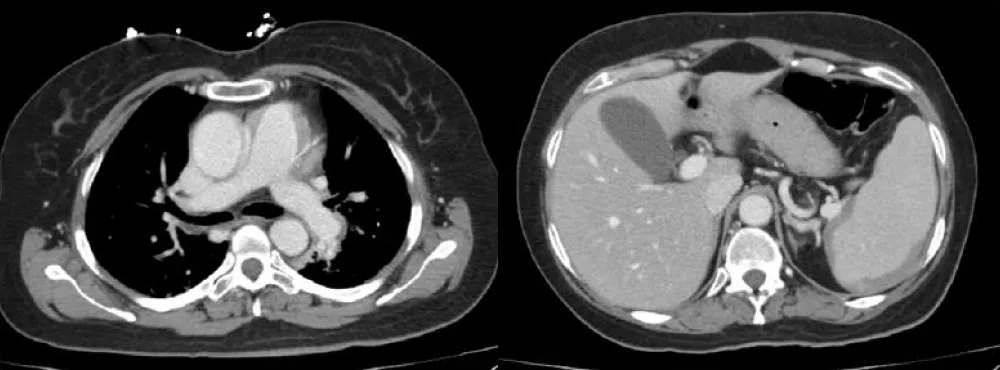

An electrocardiogram demonstrated sinus tachycardia. A chest X-ray was unremarkable, showing no infiltrates or signs of consolidation. To promptly exclude pulmonary embolism, a CT pulmonary angiogram was urgently performed. The scan revealed no evidence of pulmonary emboli, no parenchymal abnormalities, and only mild dependent atelectasis. An incidental finding of a mild subacute-chronic splenic subcapsular hematoma was noted (Figure 1).

Figure 1: CT pulmonary angiogram revealed no evidence of pulmonary emboli, with an incidental mild subacute-chronic splenic subcapsular hematoma.